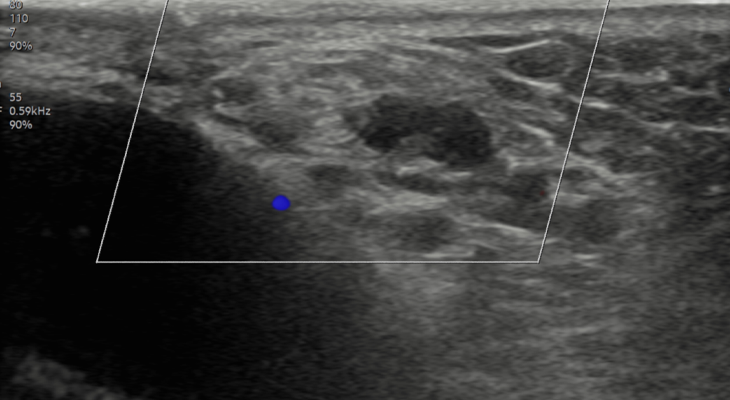

투석혈관 협착,

스텐트삽입술

시술 전

시술 후

투석중 혈류 저하,

풍선확장술로 회복

수술 후 재발된

정계정맥류 시술로 재치료